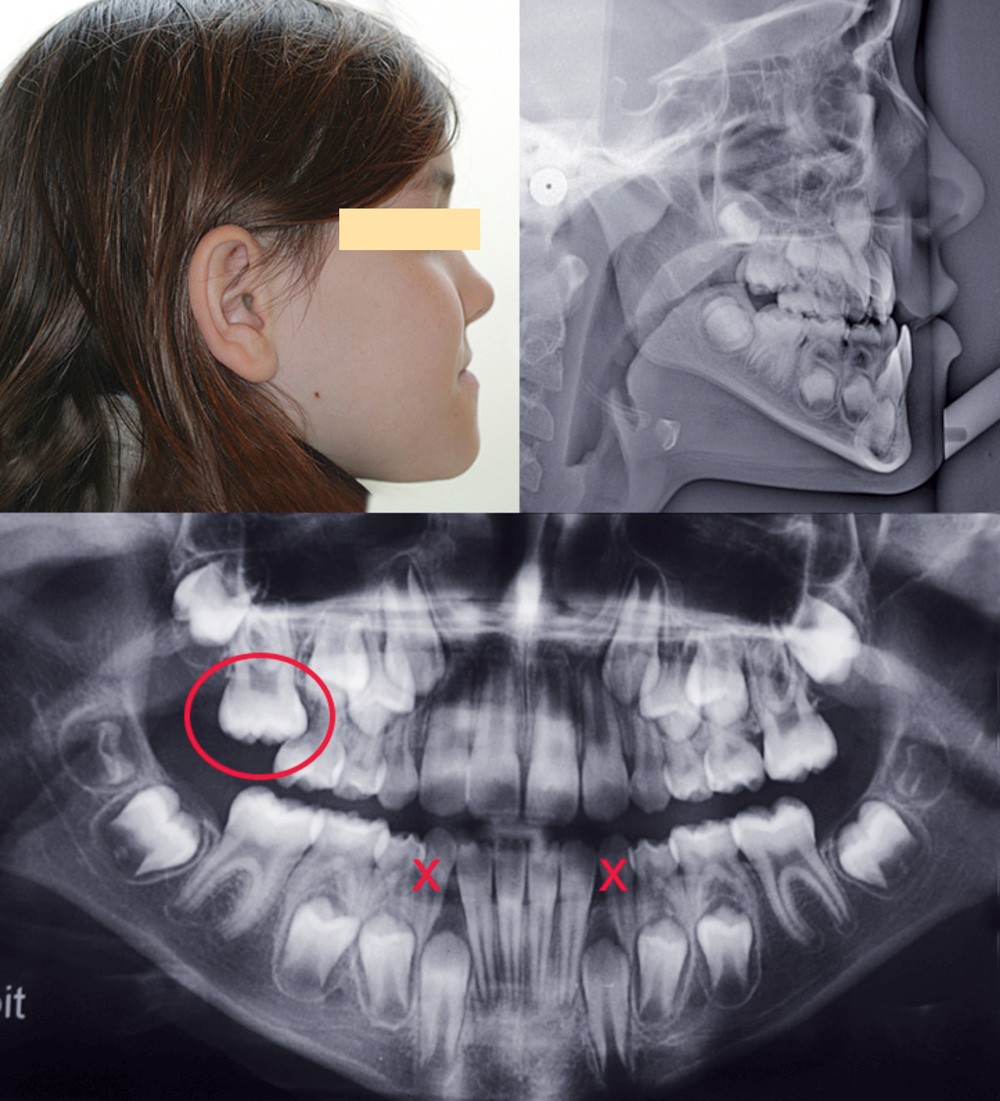

Après 6 mois d’orthopédie, la plaque au niveau du secteur I, qui a toujours été défaillante, devient mobile et finit par se débricoler. De ce fait, les élastiques du côté gauche ont davantage fonctionné ; il en résulte une déviation du milieu incisif mandibulaire à gauche (fig. 3).

Une nouvelle plaque a été fixée mais aussitôt reperdue. De ce fait, nous avons décidé de continuer avec une phase de finition multibague (fig. 4).